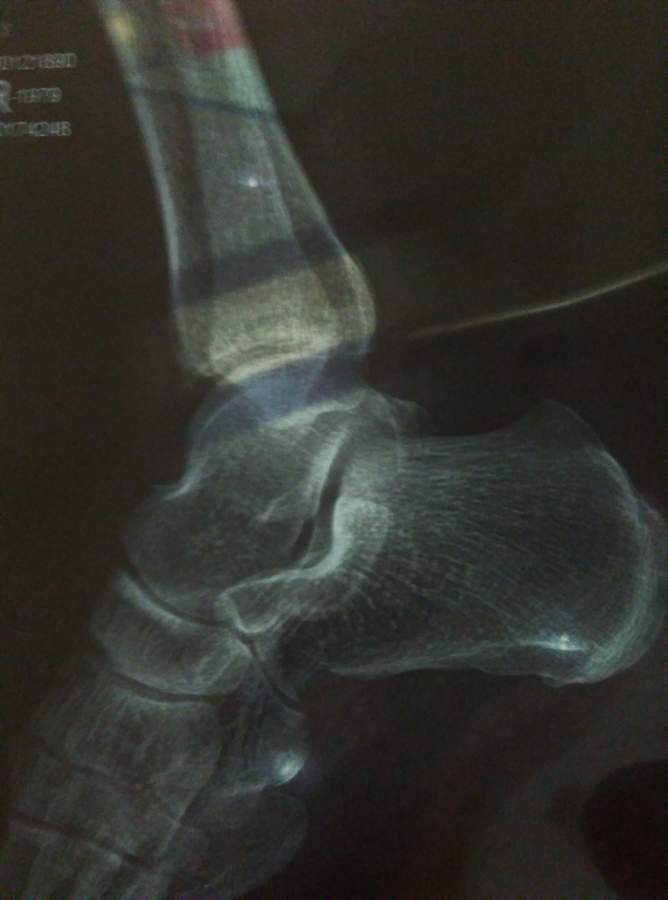

跟骨骨裂。3个月未处理,现在还是有些疼,如何处理

三个月前,取柜子上的物品时,脚踩地没有站好,当时脚踝完全没有知觉,10分钟后开始藤田,4天达到最高峰,后疼痛好转,目前已经有三个月了,还是在走路的时候有一些疼痛,昨日拍了一张X光片,医师说是骨裂,我个人也学过一点临床,对相应位置与医师观点不一致,还请各位专家指导一下 IMG_20160421_195148.jpg IMG_20160421_195147.jpg |